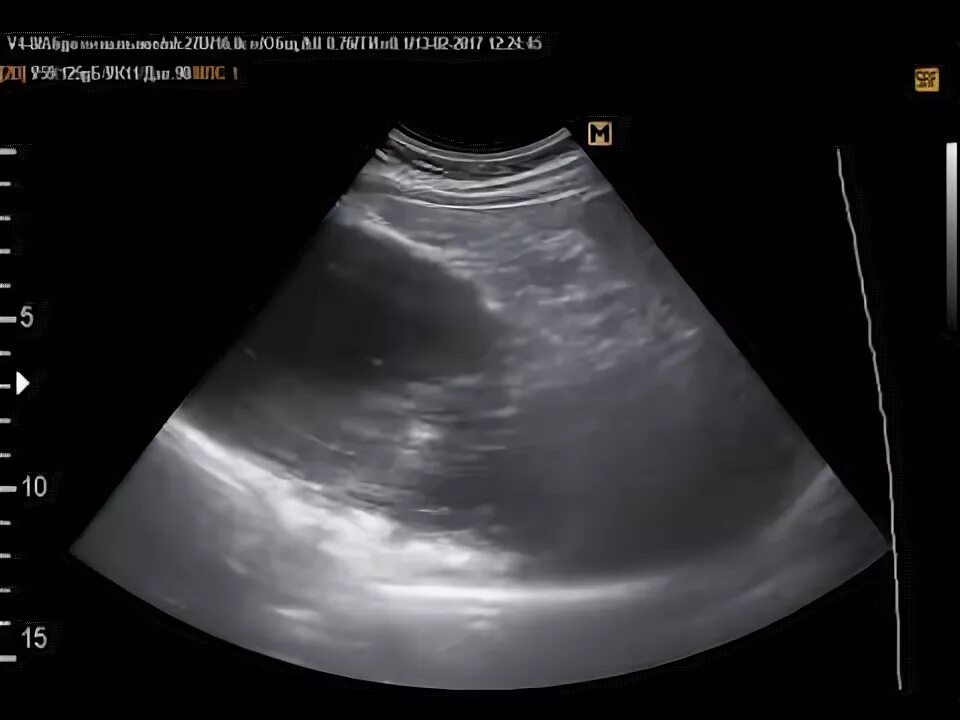

Делают узи желудка или нет